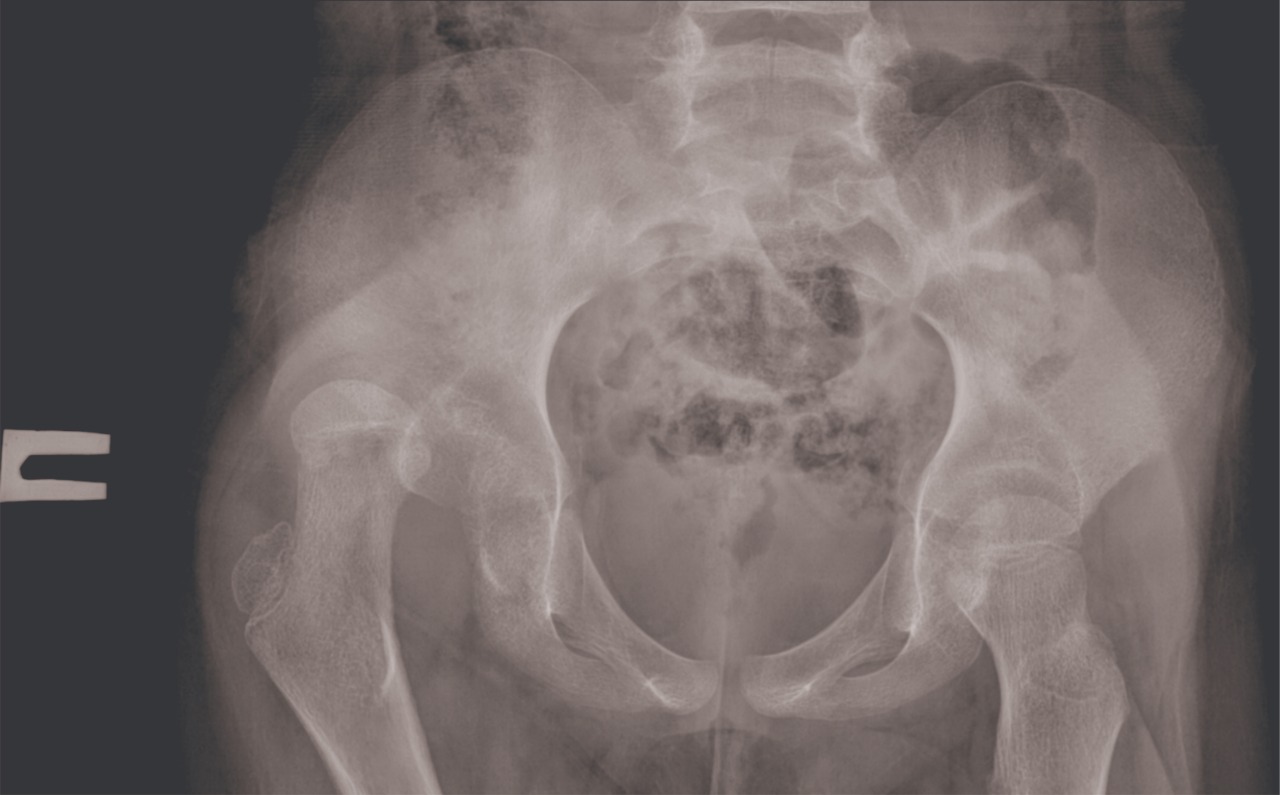

Они сообщили, что дочь жалуется на боли в районе бедра. После осмотра врачей выяснилось, что у девочки вывих кости правого бедра.

По словам родителей, девочка получила травму 17 марта после падения с алтыбакана. Ребенка лечили у народного целителя, но после были вынуждены обратиться в больницу.

Фото предоставлено пресс-службой управления здравоохранения Мангистауской области.

- На следующий день после поступления девочки врачами была проведена операция «закрытая репозиция». На данный момент ребенок чувствует себя хорошо. Пока самостоятельно ходить не может, курс лечения продолжается, - сообщили в управлении здравоохранения области.